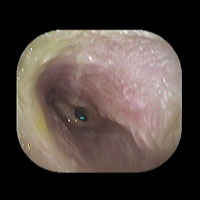

右急性中耳炎(中等症)

鼓膜がやや赤くなっています。鼓膜の奥に膿が透けて見えています。鼓膜の腫れはありません。抗生剤の内服で鼓膜切開を行わずに16日目で治りました。

初診日

7日目

14日目

16日目